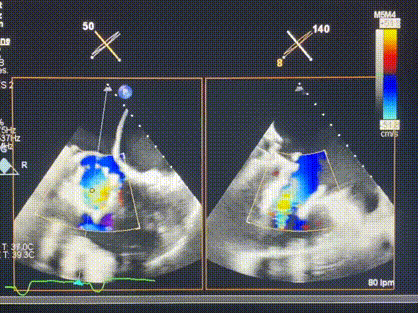

術(shù)后超聲顯示僅殘余微量瓣周漏

LuX-Valve Plus經(jīng)血管三尖瓣置換系統(tǒng)此次“出海”圓滿完成,術(shù)后Rodrigo Estévez-Loureiro教授對(duì)LuX-Valve Plus經(jīng)血管三尖瓣置換系統(tǒng)的器械性能和治療效果大為稱贊,認(rèn)為L(zhǎng)uX-Valve Plus的手術(shù)體驗(yàn)非常好。術(shù)后即刻超聲顯示三尖瓣反流幾乎完全消失,血流動(dòng)力學(xué)改善顯著,患者恢復(fù)快。在面對(duì)復(fù)雜解剖結(jié)構(gòu)、超聲影像質(zhì)量不佳、有起搏導(dǎo)線干擾時(shí),Lux-Valve Plus也體現(xiàn)了極強(qiáng)的適應(yīng)性。Thomas Modine教授和Anson Cheung教授也肯定了LuX-Valve Plus術(shù)中操作的便捷性,認(rèn)為L(zhǎng)uX-Valve Plus容錯(cuò)率高,對(duì)術(shù)中影像的依賴較小,后期希望可以更多的應(yīng)用LuX-Valve Plus三尖瓣置換系統(tǒng)于臨床實(shí)踐,讓更多的三尖瓣重度反流患者盡早獲益,改善預(yù)后。